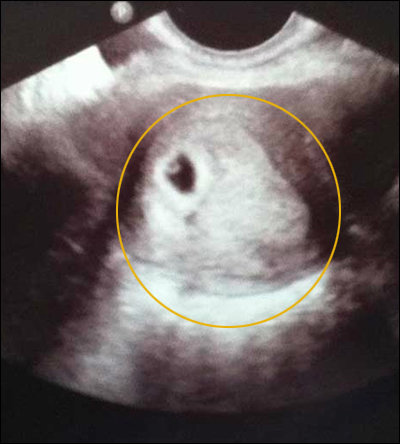

▲ 토끼 착시 초음파 사진

‘토끼 착시 초음파 사진’

‘토끼 착시 초음파 사진’이 화제다.

최근 한 온라인 커뮤니티 게시판에는 토끼와 유사한 형상이 찍힌 초음파 사진이 올라와 눈길을 끌었다.

태아의 모습이 있어야 할 초음파 사진에 우연히 토끼와 비슷한 얼굴이 찍혀 보는 이들을 경악케 한 것.

‘토끼 착시 초음파 사진’을 접한 누리꾼들은 “토끼 착시 초음파 사진 정말 신기하다”, “토끼 착시 초음파 사진, 산모 엄청 놀랐을 듯”, “합성의 냄새가 솔솔” 등의 반응을 보였다.